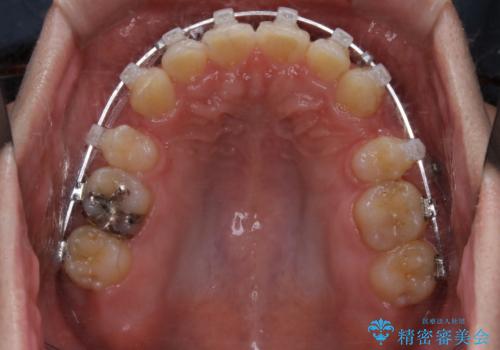

がたつき、口ゴボ(出っ歯)、真ん中のずれを抜歯矯正治療で治す。ワイヤー矯正治療

- 矯正装置

- ワイヤー矯正 審美装置

- 治療計画

- 口元の突出感とがたつきを気にして来院されました。

突出感とがたつきの改善を行うために大きなスペースが必要であったため、親知らず以外の歯を4本歯を抜歯する計画を立てました。

移動量が大きいこと、また、患者さんの生活習慣的にマウスピース装着が難しそうとの理由から

ワイヤー表側矯正装置で治療を行うことになりました。